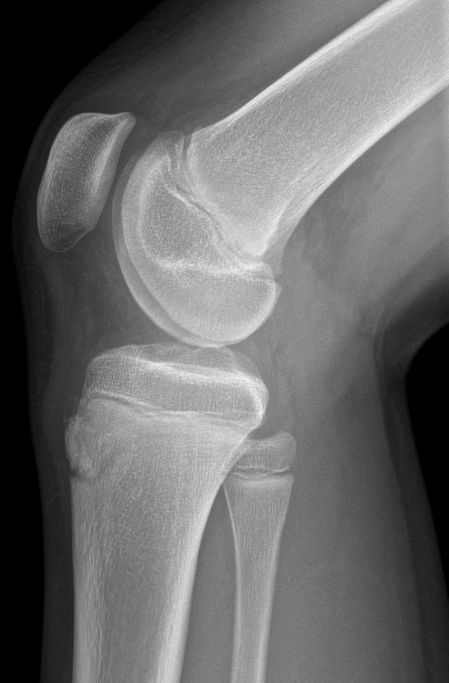

- Slätröntgen med sidobild av knä, kan visa visa benfragment i tuberositas tibiae [1]

Exempel på diskreta schlatter-förändringar i tuberositas tibiae